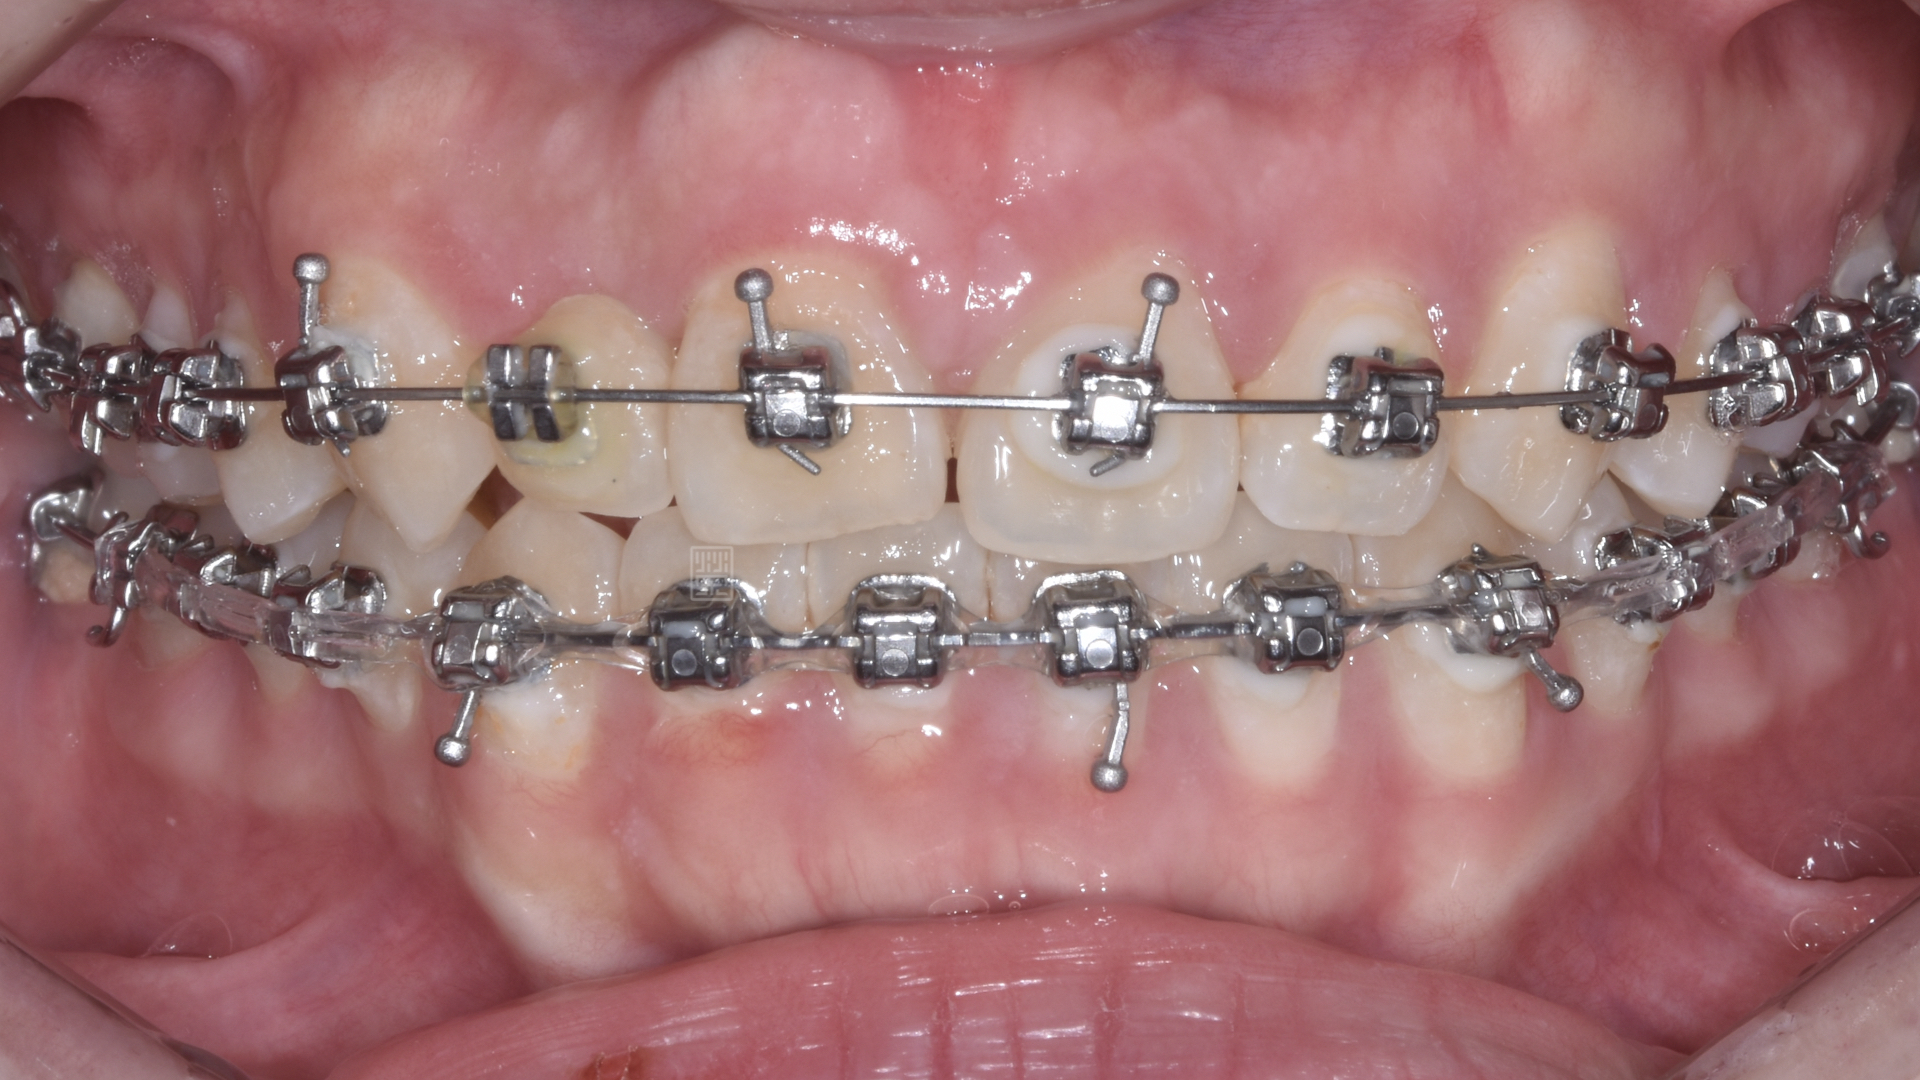

矯正移出側門牙空間

皮質骨切開手術增加牙齒移動

矯正時因牙齒沾黏骨頭無法移動